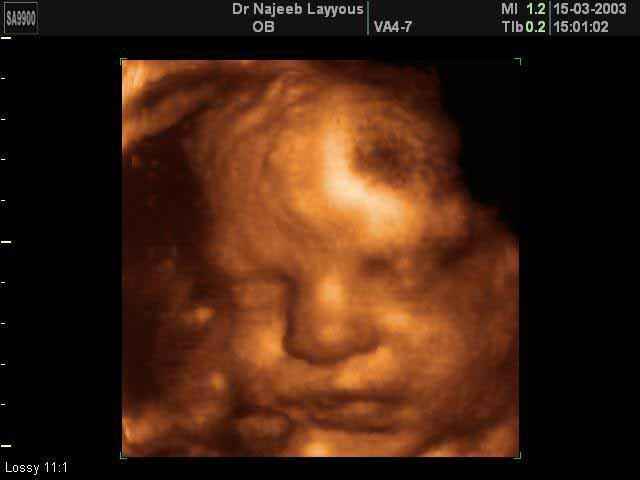

3D Fetal Face Ultrasound Scan Photos